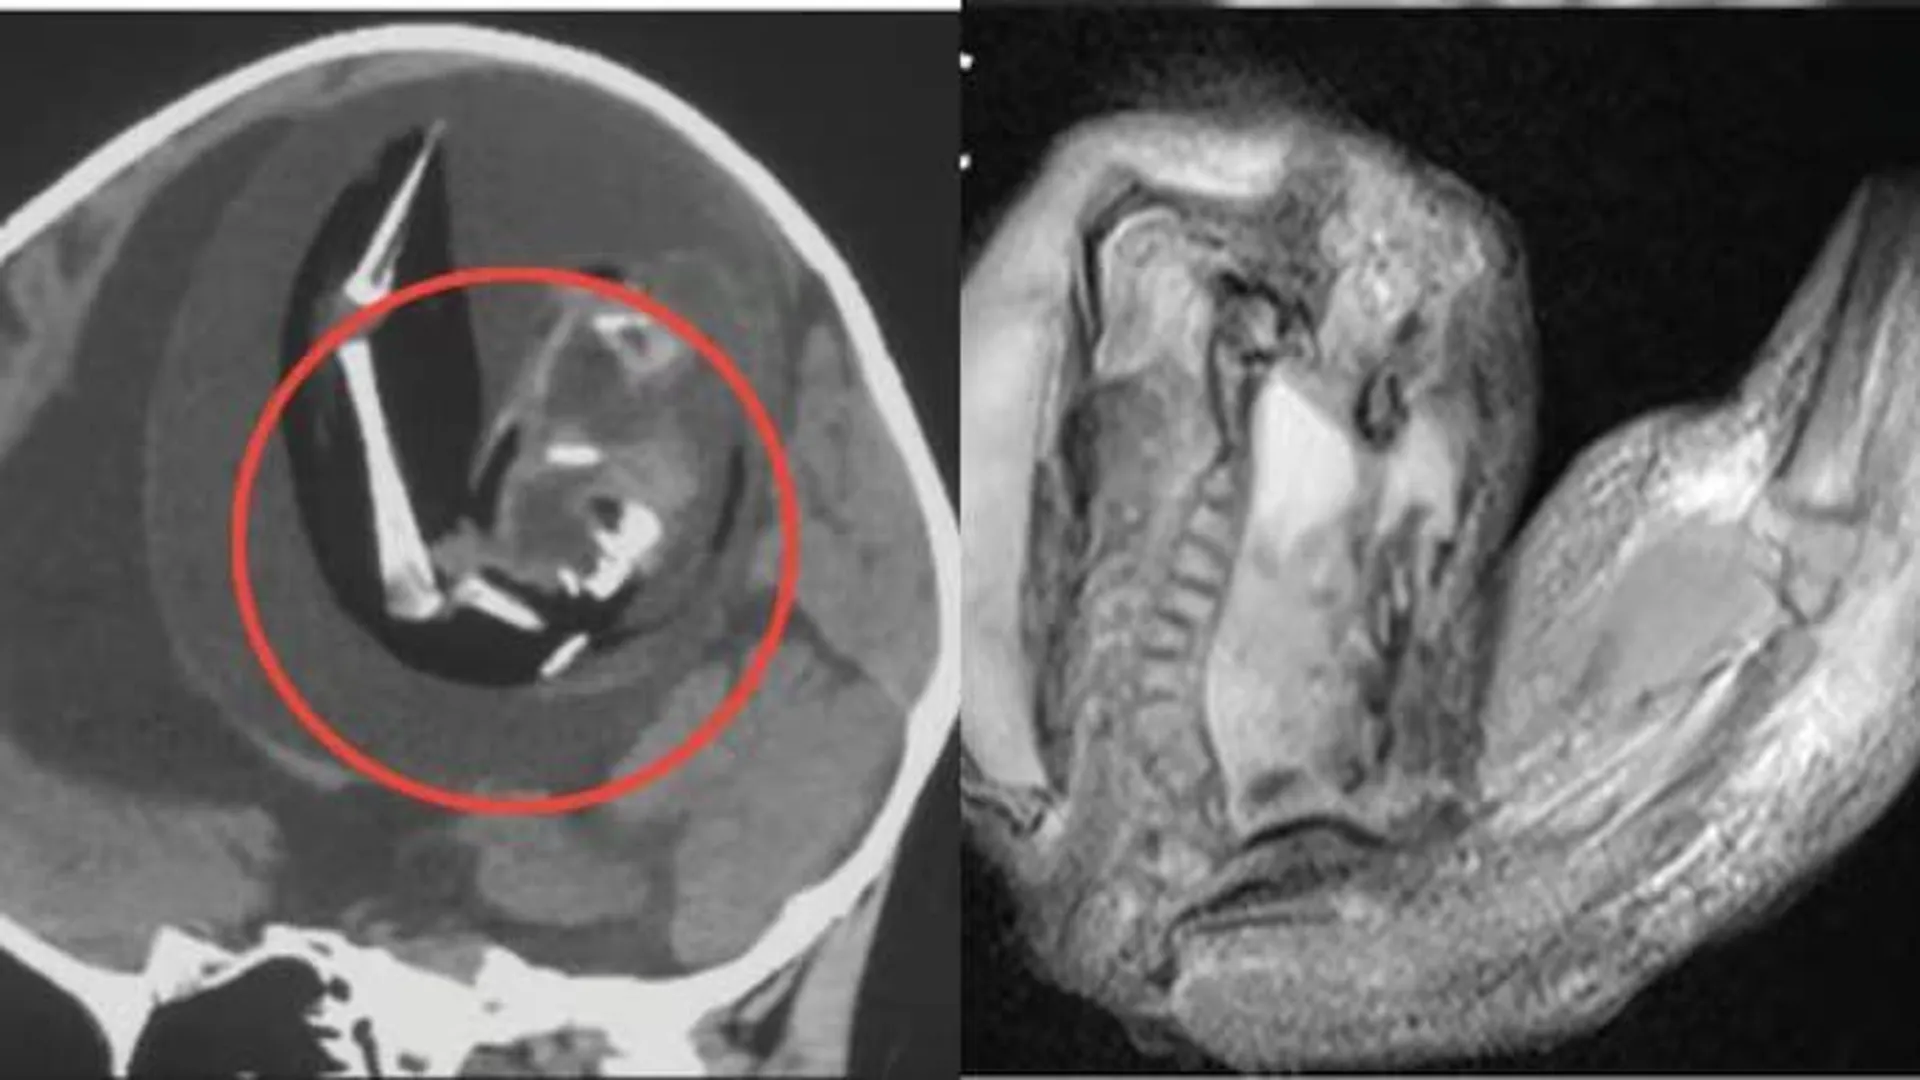

ବର୍ଷକର ଶିଶୁ ମସ୍ତିଷ୍କରୁ ଯାଆଁଳା ଭ୍ରୂଣ ବାହାର କଲେ ଡାକ୍ତର